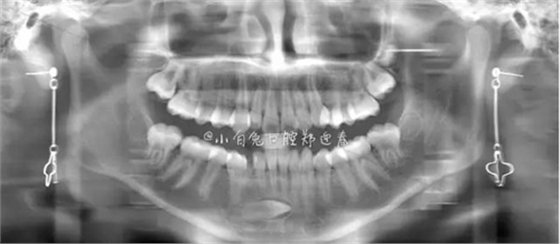

本案:患兒,女,14歲,因牙齒矯正來(lái)院,檢查見(jiàn)83滯留,43未見(jiàn)萌出,拍片發(fā)現(xiàn):43埋伏阻生于31、41、42根尖下方,按照正畸診療計(jì)劃,擬行43拔除術(shù)。

全景片